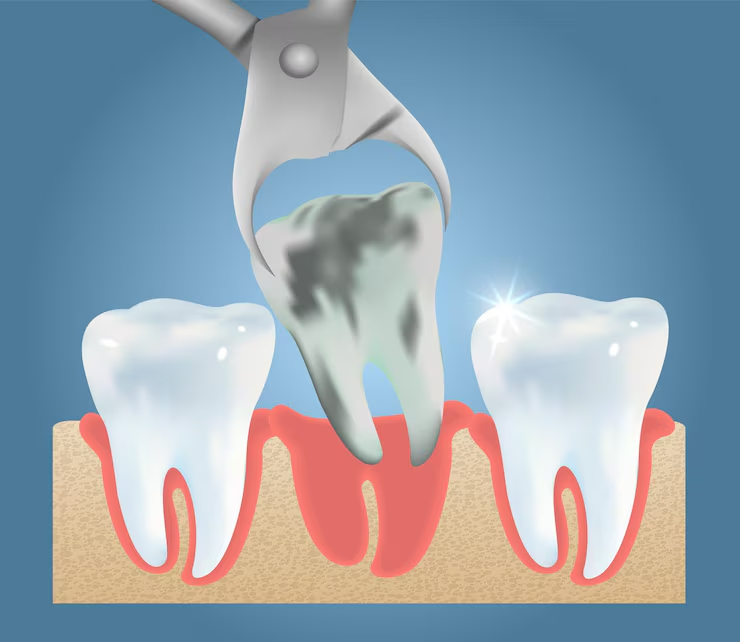

Precautions to Take After Wisdom Teeth Removal Wisdom teeth removal is a common dental procedure that many people go through, especially in their late teens or early twenties. These “third molars” are the last teeth to erupt and can sometimes cause more trouble than...